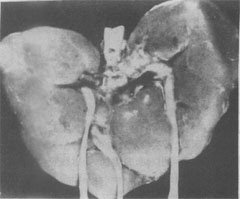

图6-2 21三体核型与正常核型比较 上图 21三体(Down)综合征下图 正常核型 (2)Edwards综合征:染色体异常为18三体。表型特征有智力低下、小头、前额窄、枕部突、小颌且张口范围小,腭弓高窄、低位耳、肾畸形(图6-3)、肌张力增高及手紧握等(图6-4)。

图6-3 18三体(Edwards)综合征的畸形肾 图示马蹄状融合肾及额外输尿管